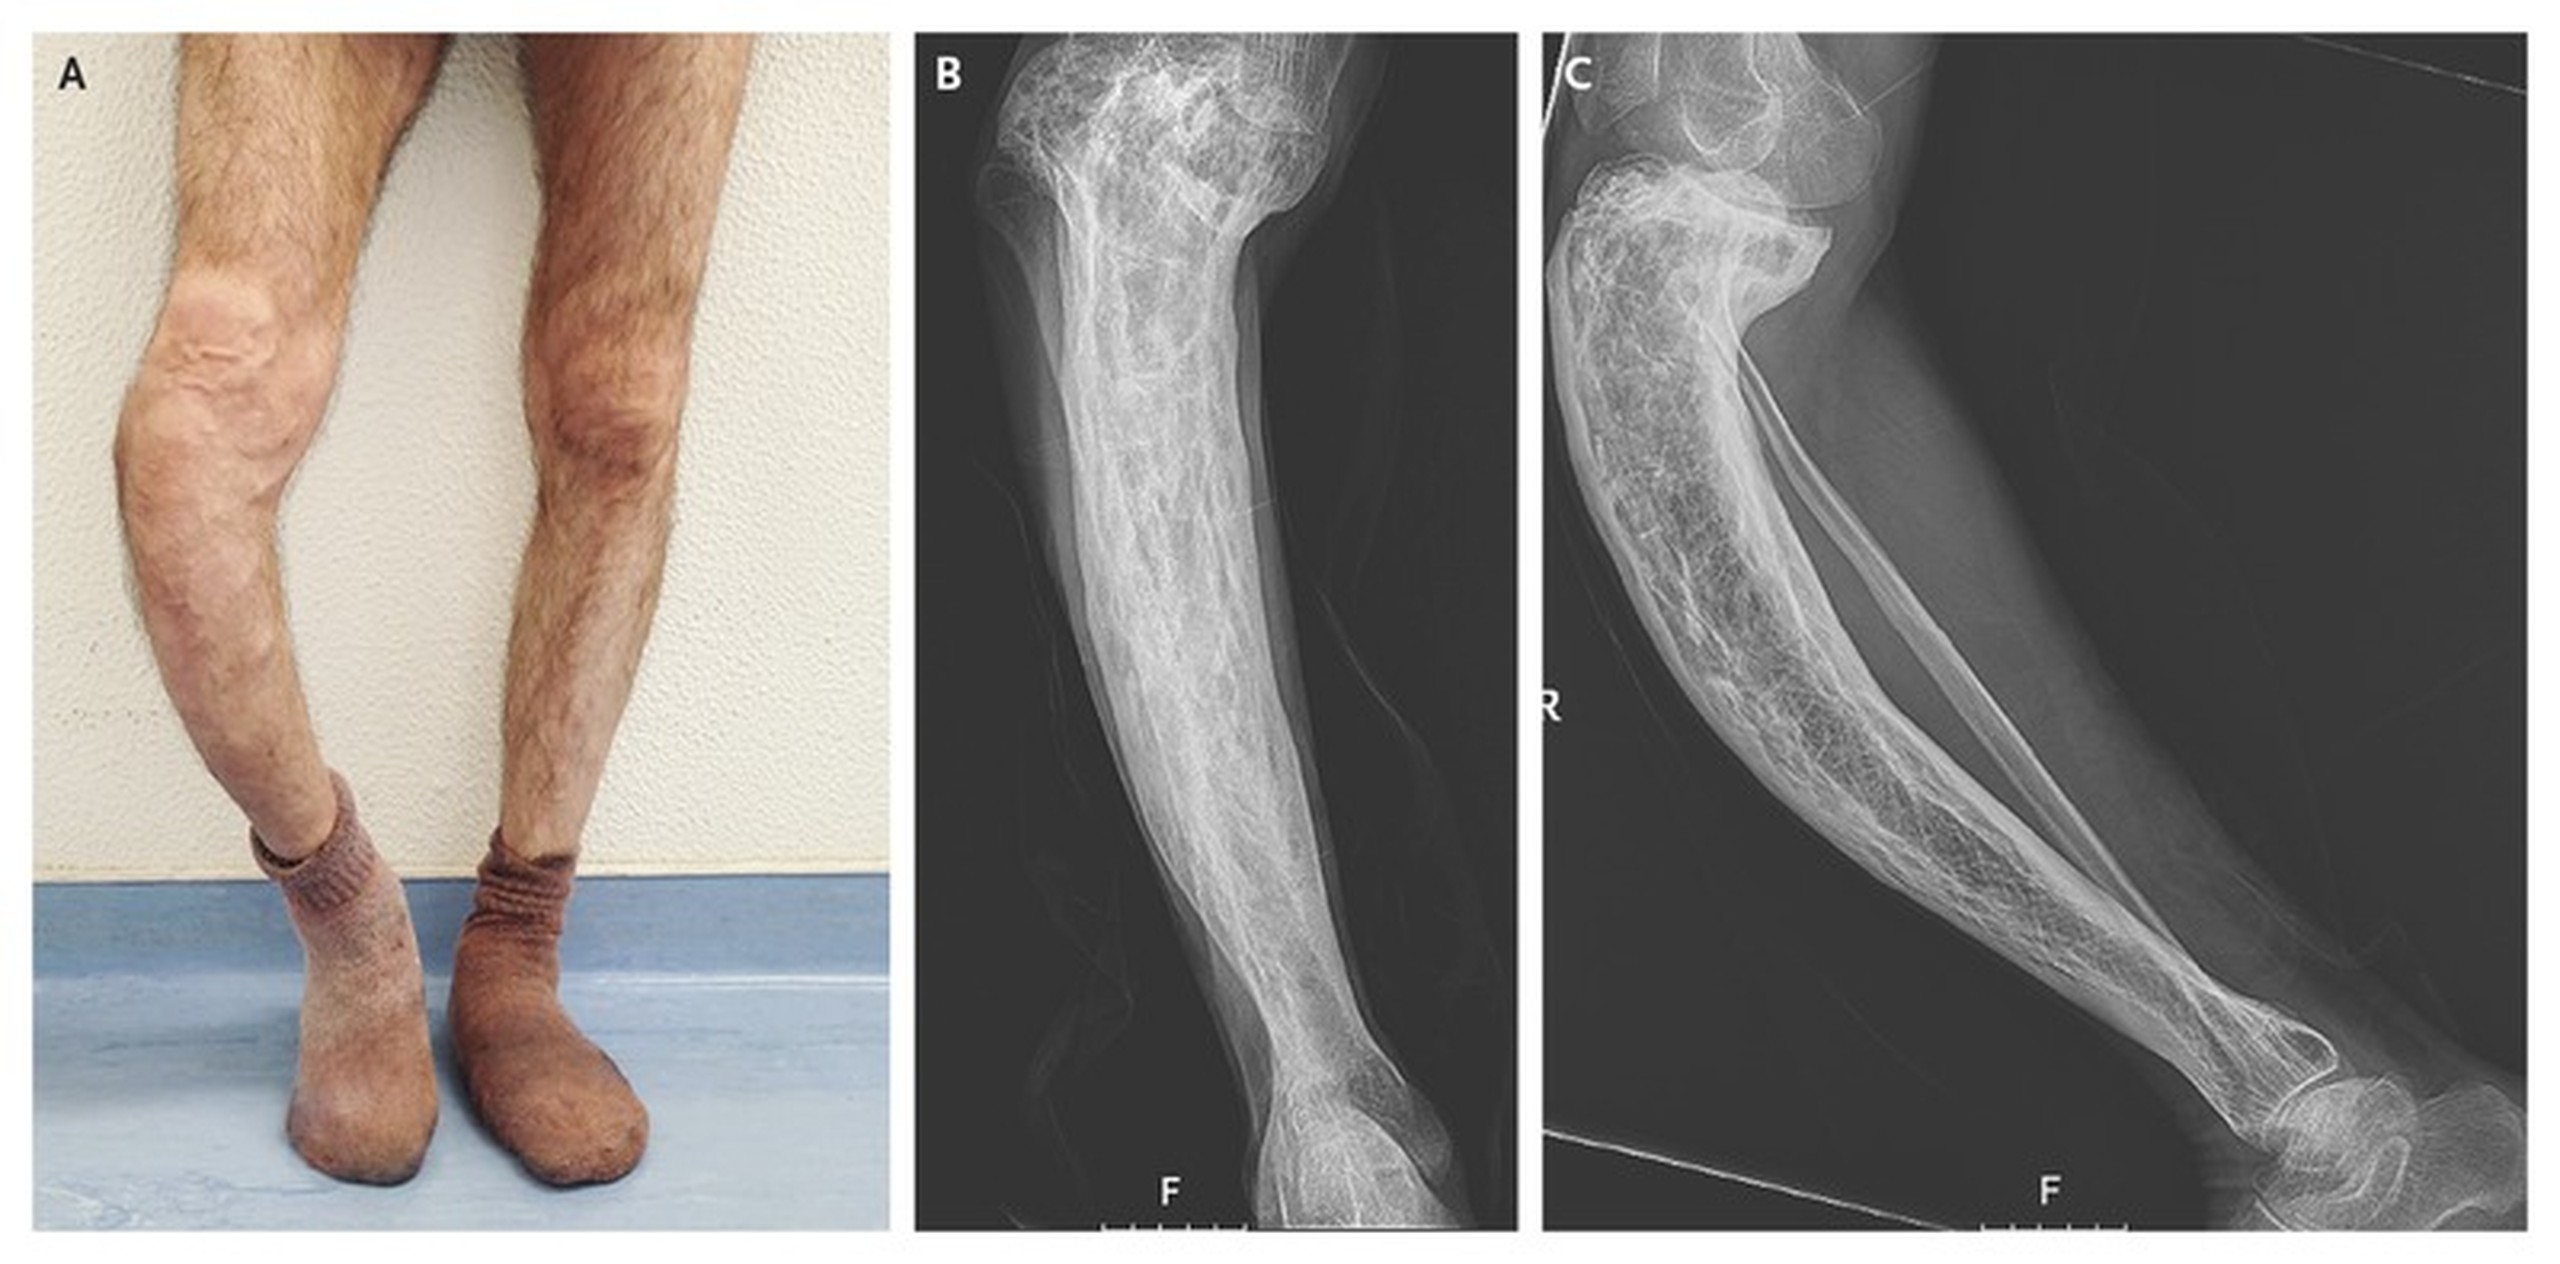

• Tăng kích thước đầu, cong chi hoặc cong cột sống. Điều này có thể xảy ra trong các trường hợp nâng cao.

Gãy xương và dị tật: Xương bị ảnh hưởng dễ gãy hơn, và các mạch máu thừa trong những xương bị biến dạng này khiến chúng chảy máu nhiều hơn trong quá trình phẫu thuật. Xương chân có thể bị vòng kiềng, có thể ảnh hưởng đến khả năng đi lại.